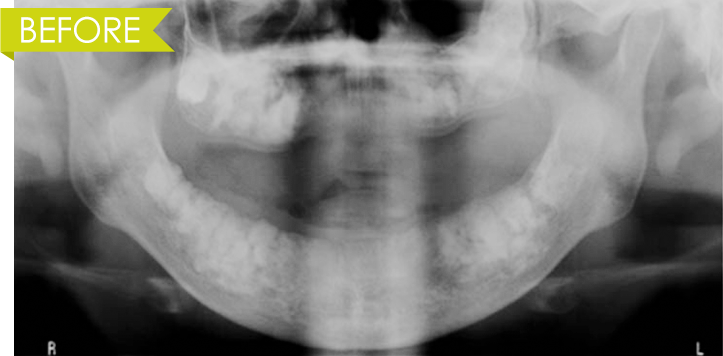

정밀진단과 구강검사

상실된 치아와 3차원 CT와 X-ray촬영

및 잇몸뼈 상태를 체크 합니다.